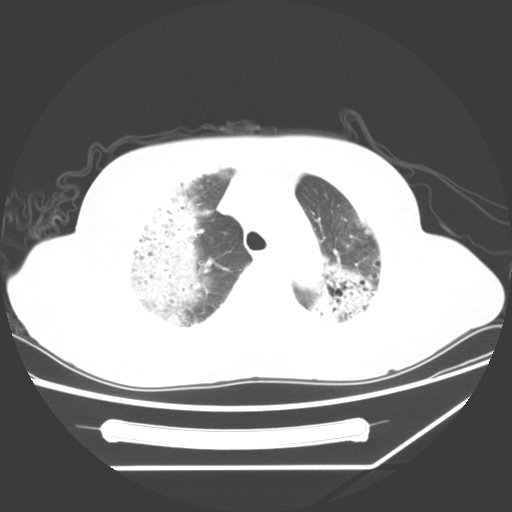

标题: CT25393:病人45岁,咳嗽,吐黄痰带血丝,发热,胸闷月余 [打印本页]

标题: CT25393:病人45岁,咳嗽,吐黄痰带血丝,发热,胸闷月余

1、左肺中央型肺癌并双肺弥漫性转移   2、双肺部感染    3、肺大泡     4、左侧胸腔积液

双侧肺弥漫性病变,可见“空泡征”及“蜂窝征”,考虑肺泡癌可能性大,左侧胸腔积液,考虑胸膜受累可能!

考虑肺泡癌,建议排除感染。

考虑肺泡癌

1)不排除肺泡癌可能。2)左侧胸腔积液。